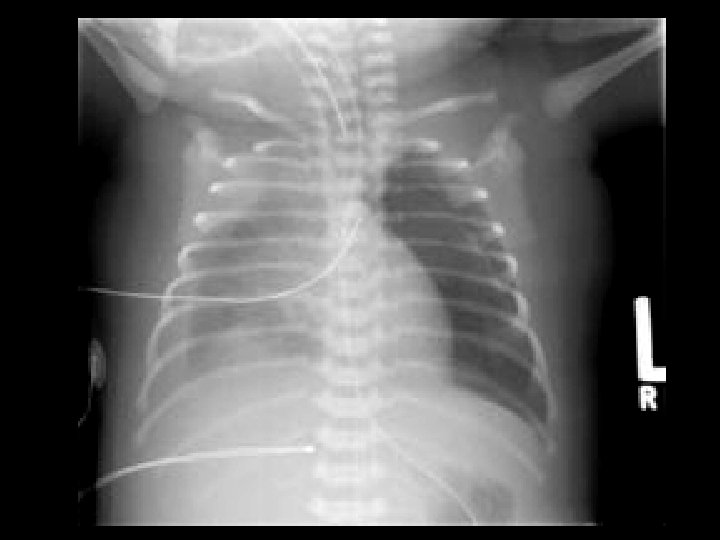

Pulmonary Interstitial Emphysema (PIE) • Findings: – unilateral hyperinflation causing mediastinal shift – small distinct cyst-like lucencies distributed uniformly • Complication of mechanical ventilation in neonates with respiratory distress • Extra-aveolar interstitial air can compromise ventilation and perfusion • Frequently complicated by pneumothorax and pneumomediastinum